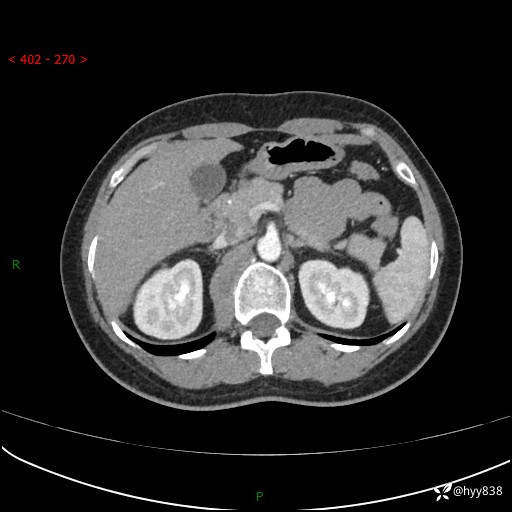

简要病史:患者于1天前因体检发现右旁肾占位,无肉眼血尿,无畏寒发热,无咳嗽咳痰,无腰腹部疼痛不适,无尿频尿急症状,起病来,患者未行特殊治疗,为求进一步诊治,门诊以"右侧腹膜后肿物"收治入院。 发病来患者精神、饮食、睡眠良好,小便如上,大便正常,体重无明显变化。

辅助检查:CT

临床诊断:腹膜后肿物

上腹部CT增强(动脉期+实质期)(外院平扫)